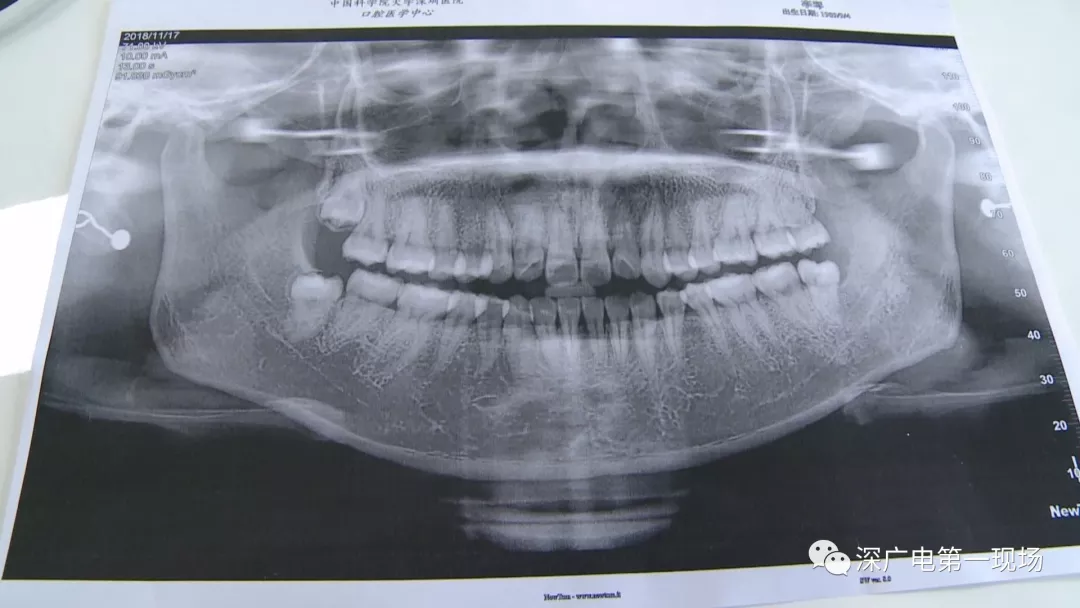

拔一顆智齒一千六?! 深圳這位女士默默的放下了賬單……

隨后,李女士在網(wǎng)上查詢,發(fā)現(xiàn)拔智齒的收費都是參差不齊,也沒有參考標準。在李女士提供的拔牙收費單上,記者注意到,除了一些拔牙必用的藥物外,還有一些輔助工具的費用。

中國科學院大學深圳醫(yī)院口腔科主任賈岳介紹,對于不同患者的牙齒,它的治療方法都不一樣,所以不同牙齒,醫(yī)院收費的標準也各不相同。牙齒的治療方案,都是根據(jù)患者牙齒具體情況來制定,然后再去收費,同時也會參考病人實際情況來做不同的治療項目。